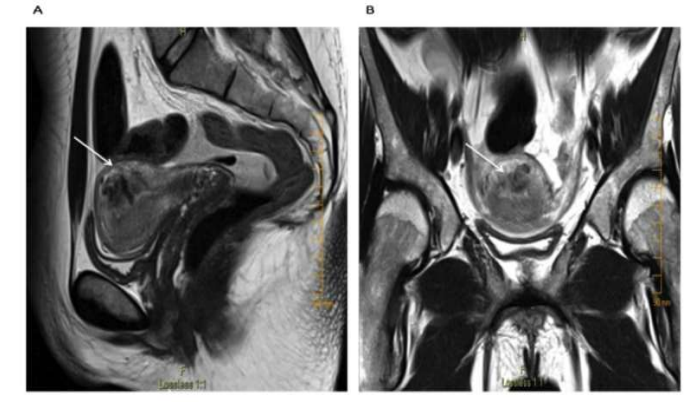

Shintre and Coelho [16] reported a 27-year-old lady who was known to have Thalassemia minor who had manifested with heavy vaginal bleeding and passage of clots over the preceding two days. She stated that she had been having continuous on and off mild to moderate vaginal bleeding pursuant to a second trimester therapeutic abortion she had undergone two months preceding her presentation. She did undergo therapeutic abortion in view of the fact that she had her chorionic venous samples which had shown that the foetus had Thalassemia major due to the fact that both herself and her husband had Thalassemia minor. The therapeutic abortion was induced with utilization of misoprostol (PGE1) tablets. The reports of the obstetrician who undertook the therapeutic abortion did document that the abortion was complete and therefore no curettage was undertaken pursuant to her abortion. She had also undergone another therapeutic abortion 8 months earlier for the same reason following chorionic villous sampling that showed Thalassemia major foetus. This therapeutic abortion was ensued by curettage of her uterine cavity for complete evacuation of her products of conception. She did not have any significant past medical or surgical history. She was noted to be pale or otherwise her general examination was normal. She had speculum examination of her vagina which showed a partially open cervical os that associated with minimal blood clots. There was no active bleeding. Her uterus was bulky, and it measured about 8 weeks to 10 weeks size as well as it was firm to soft in consistency, firm to soft with regard to consistency, mobile and associated with free fornices. The results of some of his laboratory blood tests included: Haemoglobin 9.5 grams per decilitre, platelets 3-lakhs, Serum Beta Human Chorionic Gonadotrophin (B-HCG) 35 MIU/ML which was normal, normal coagulation screen and normal liver function tests. Her blood sample was sent for grouping and saving for future use when required. She had ultrasound scan and magnetic resonance imaging (MRI) of pelvis. The MRI scan demonstrated a bulky uterus that measured 4 cm x 7 cm x 7 cm, heterogeneous lesion within the posterior wall of her uterus, lost endometrial-myometrial interface, multiple dilated tortuous blood vessels within her posterior myometrium which had suggested the likelihood of retained products of conception or gestational trophoblastic tumour which would represent placental site trophoblastic tumour, or uterine vascular malformation (see figure 1). The trans-abdominal ultrasound scan of pelvis did demonstrate an 8.8 cm x 7.5 cm x 7.5 cm bulky uterus the posterior myometrium that was very enlarged as well as heterogeneous with increased vascularity upon Doppler ultrasound scanning (see figure 2). Doppler ultrasound scanning did demonstrate a peak systolic velocity (PSV) of 121 cm / s as well as restrictive index of 0.36. The ultrasound scan also demonstrated that her endometrium was thickened within the lower uterine segment that was suggestive of retained products of conception. She had a chest x-ray which was normal. She had ultrasound scan-guided evacuation of her retained products of conception from her lower uterine segment which was sent for pathology examination. The evacuation of the products of conception did trigger active bleeding. She therefore underwent uterine artery embolization with utilization of cyanoacrylate (glue) (see figure 3). There was no evidence of active bleeding pursuant to her embolization. She was discharged on the 3rd post-procedure op day on oral antibiotics and haematinics. Pathology examination of the tissue did show degenerated and necrosed bits of decidua as well as few degenerate chorionic villi that were admixed with fibrin and blood. The degenerate products of conception did not show pathology examination features of placental site tumour trophoblastic. At her 6-weeks follow-up assessment she stated that her vaginal bleeding had diminished gradually over a period of 4 weeks and the bleeding stopped completely after 4 weeks. She had ultrasound scan of her pelvis with Doppler scan which did show diminished size of the arteriovenous fistula and with diminished vascularity (see figure 4). Shintre et al. [16] stated that the first case of AVM of the uterus was reported in 1926. [17]

MRI pelvis-sagittal and transverse section-showing bulky uterus with 4 x 7 x 7 cm sized heterogeneous lesion seen in posterior wall, lost endometrial-myometrial interface, multiple dilated tortuous blood vessels in posterior myometrium & tiny enhancing area within the endometrium in lower uterine segment. Reproduced from: [16] Shintre H S, Coelho K S. Managing Uterine Arteriovenous Malformation (AVM) Is Like Dealing with Raging Wildfire Awaiting A Spark: Better Be Extremely Cautious & Be Ready with Counter Measures Like Uterine Artery Embolization (UAE). Obstet. Gynecol. Int. J. 2017; 6(1): 00195 DOI: 10.15406/ogij:2017.06.00195

https://medcraveonline.com/OGIJ/managing-uterine-arteriovenous-malformation-avm-is-like-dealing-with-raging-wildfire-awaiting-a-spark-better-be-extremely-cautious-amp-be-ready-with-countermeasures-like-uterine-artery-embolization-uae.html under copy right ©2017 Shintre, et al. This is an open access article distributed under the terms of the, which permits unrestricted use, distribution, and build upon your work non-commercially.

Khan et al. [24] reported a 30-year-old G1P0010 lady wo had manifested with a 6 days history of abnormal bleeding from her uterus. Three months preceding her presentation, she had undergone a therapeutic abortion which was ensued by dilatation and curettage (D&C) for retained products of conception. Since then, she realised that she had developed a new onset of menorrhagia, which on the day of her manifestation had become persistent and which had become associated with severe pain, weakness, as well as dizziness. Upon her examination, she was observed to be hypotensive, and she had tachycardia. She had marked tenderness within her supa-pubic region. Her examination was otherwise normal. Some of the results of her laboratory blood tests included: haemoglobin 9.2 grams per decilitre, haematocrit 27.5% and negative serum Beta Human Chorionic Gonadotrophin (B-HCG). She trans-vaginal ultrasound scan which showed a 3.9 cm x 2.7 cm x 1.8 cm sized an-echogenic cystic spaces within the posterior wall of the fundus of her uterus (see figure 8). She had Doppler ultrasound scanning which revealed marked vascularity within her uterus (see figure 9). She had magnetic resonance imaging (MRI) scan of pelvis which showed a contrast-opacified structure within structure within the wall of her myometrium. Focal serpiginous flow voids were also demonstrated within the posterior-superior myometrium with extension to the canal of her myometrium (see figure 10). The features of the radiology were interpreted to be consistent with the diagnosis of arteriovenous malformation of the uterus (AVMU). She had uterine angiogram which confirmed features of arteriovenous malformation of the uterus (AVMU) within the posterior-superior wall of the uterus (see figure 11). The angiogram did demonstrate presence of multiple feeding arteries which had arisen mainly from the left with smaller arteries from the right side. Embolization of both uterine arteries was undertaken with utilization of Gelfoam (Pfizer, New York) pledgets to near stasis. She had a post-embolization arteriogram which demonstrated complete embolization of the AVMU as well as evidence of slow flow of contrast in both uterine arteries. No immediate complications emanated. Her vaginal bleeding stopped. She was discharged home on her 3rd day post-embolization. During her follow-up assessment, 3 weeks pursuant to her embolization there was no evidence of recurrence of abnormal uterine bleeding. The lesson that has been learnt from this case report is that embolization of the uterine artery supplying the AVMU is an effective minimally invasion option of treating AVMUs.

Figure 10: T2-weighted pelvic magnetic resonance imaging (MRI) revealing a hypo-intense T2 lesion within the posterosuperior wall of the myometrium: (A) sagittal view (B) axial view. Reproduced from: [24] Khan S, Saud S, Khan I, Achakzai B. Acquired Uterine Arteriovenous Malformation Following Dilatation and Curettage Treated with Bilateral Uterine Artery Embolization: A Case Report. Cureus. 2019 Mar 13;11(3):e4250. doi: 10.7759/cureus.4250. PMID: 31131173; PMCID: PMC6516630. https://pubmed.ncbi.nlm.nih.gov/31131173/ under Copyright © 2019, Khan et al. This is an open access article distributed under the terms of the Creative Commons Attribution License, which permits unrestricted use, distribution, and reproduction in any medium, provided the original author and source are credited.